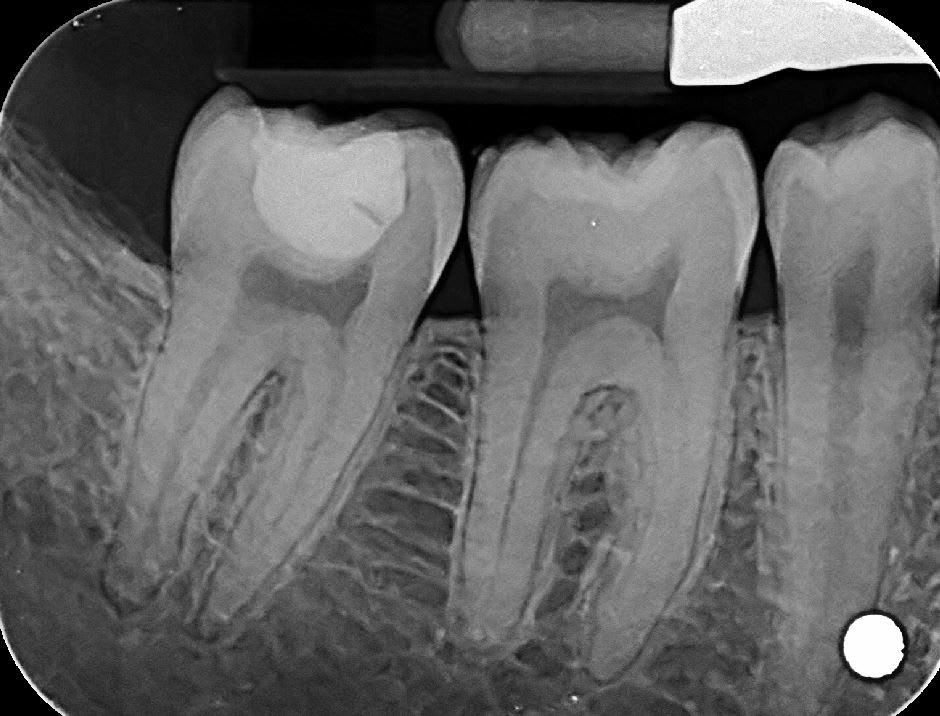

du coup j'ai revu le patient

j'ai démonté le soin, j'ai vu le fond de cavité que j'ai deposé mais pas de carie dessous visible

j'ai remis de la résine sans fond de cavité,

J'ai prévenu le patient des risques de sensibilité post op qui pouvaient venir à cause de fait que j'ai déposé le fond de cavité. Et que s'il y avait des sensibilités, il faudrait dévitaliser la dent.

Tu vois , ils se foutaient de notre tronche quand on disait qu’ il y avait un fond de cavité sans carie :) Ils m’ont même mis le doute les deux:)

Perso j aurais jamais pensé voir un truc aussi propre... j' avais vraiment tort. Désolé...

Je pensais trouver une dentine noire ébène... Ramollie mais assez dure... De la carie a progression très lente.

Du coup c'était quoi le fond de cav ?? Ça sentait l eugenol ??

Du coup le patient est revenu pour un sc7+z3 ?? C est pas vraiment rac0 ready cette histoire.

Fallait faire un inlay 1F.